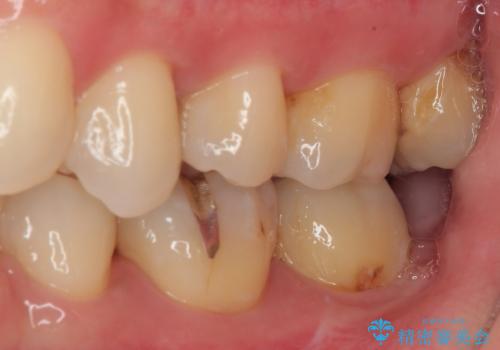

歯列が移動したとはいえ、左右ともに後方傾斜しており、むし歯の除去、形成(形を整える)、型取りの全てが非常に困難な処置となりました。

セラミッククラウンの適合はレントゲン写真からも分かる通り、境界がぴったりと合った、高適合のものとなりました。